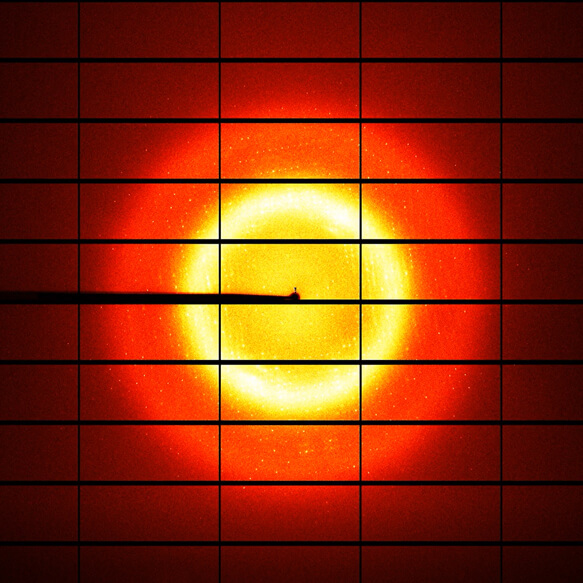

The piece will take the form of a composition of genetics labs with their unique signage and equipment, files of legal documents related to genetic engineering, and a facial recognition booth that identifies vital parts of the viewers’ identity. Most excitingly, it will also portray The Antibody Room, featuring the development of an artificially engineered antibody that bears the name “Lynn Hershman” in its molecular structure. A project was developed in collaboration with Novartis and inspired by today’s leading scientific research.

Besides their widely known role as immune molecules and vaccines, antibodies have become a central tool for biotechnology and biomedicine and are well-established therapeutic modalities in the Novartis portfolio. Hershman worked alongside Dr Thomas Huber (the therapeutic antibody research group leader in Novartis) to create this new antibody. And, as it’s standard in biotechnology laboratories after the antibody was designed, it was subjected to a series of research experiments to discover its properties and potential therapeutic or research applications. Still undergoing investigations, it will be interesting to know what molecule this antibody targets and whether it is involved in any disease or therapeutic pathway (some preliminary results will be revealed on April 24, Dr Huber shared with us).

Thomas: Lynn Hershman approached Novartis to gain more insight into antibody discovery processes and applications. To explain our research activities and to personalise what Novartis is doing in research, the idea was created to design a novel antibody. Antibodies are made up of amino acids. There are 20 naturally occurring amino acids, typically abbreviated by a letter, e.g. leucine = L. The novel antibody will reflect Lynn’s name in its amino acid sequence, making up the region usually important for recognising antigens.

The Lynn Hershman region of the antibody will mediate its unique character. Our part was designing, producing and profiling the antibody and generating data and reports of the process. We will further provide some scientific equipment and the actual LYNN HERSHMAN antibody for the exhibition. It would be great if the LYNN HERSHMAN antibody project may trigger some thoughts and excitement around the field of therapeutic antibodies in one or the other visitor.

Therapeutic antibodies typically aim at extracellular (secreted or cell membrane-bound targets). For the Lynn Hershman antibody, we have indeed chosen a fluorescence-based assay based on a recombinant protein CHIP array with around 7000 different secreted proteins spotted. However, Swiss TV wished we would evaluate the CHIP experiment only when Lynn visits on April 24. Thus, we don’t know the results yet.

A therapeutic antibody optimally recognises the single protein for which it was selected and is not binding to any other. For the Lynn Hershman antibody, we defined the sequence of the antibody and are probing for a potential binding specificity. Due to the long critical loop, I expect it may bind weakly to various proteins. If we saw a more defined specificity or no binding to any proteins, that would be extraordinary. But we have to see… So it still is an exciting experiment to run.